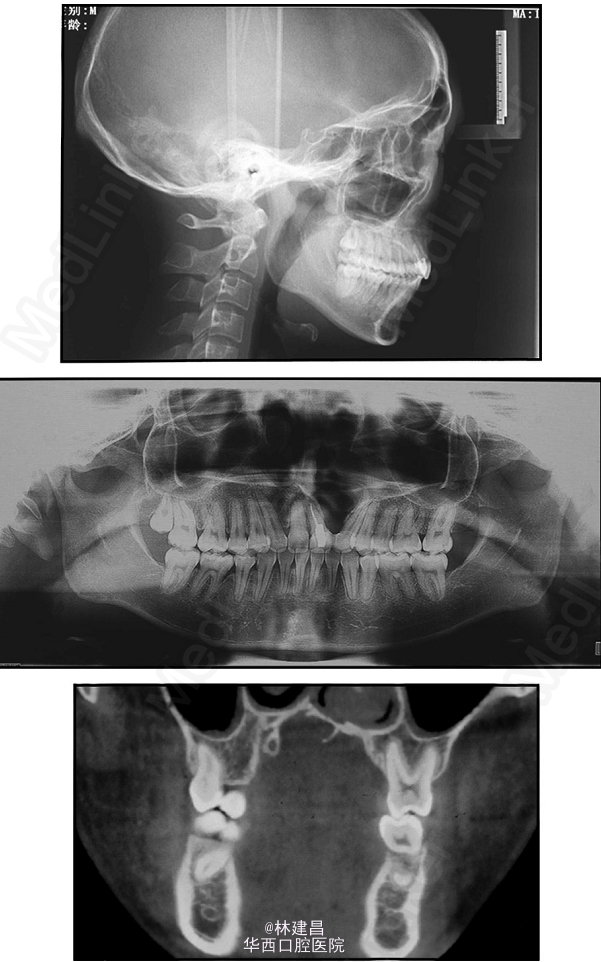

患者为18岁男性,面形凹,上颌骨发育不足,有一处重度牙槽突裂,因面部不美观,来正畸科求治。综合评价其病情后,为患者提供了手术和非手术两种方案,患者最终决定了非手术方案。此后患者的正畸治疗包括了扩弓、拔牙和牙周修复会诊。正畸治疗使用了新亚MBT托槽0.022x0.028(国产托槽也有好货!)配合微种植钉,排齐整平恢复I类磨牙关系。治疗完成1年后复诊。